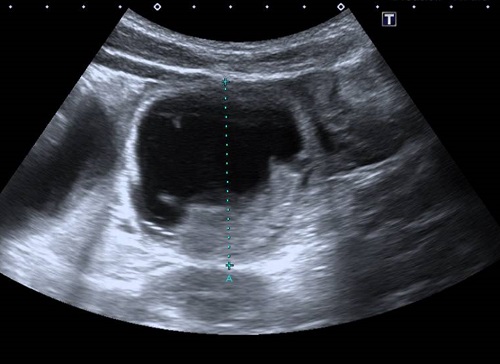

Durante su estancia en urgencias realiza varios vómitos biliosos, que muestran refractariedad a la administración de ondansetrón IV. Además, progresa en intensidad el dolor abdominal y sigue sin emitir heces. Se solicita radiografía de abdomen, donde se observan asas de intestino delgado dilatadas en mesogastrio e hipocondrio izquierdo con material fecal en colon ascendente y presencia de gas distal, imagen sugerente de obstrucción de intestino delgado (Fig. 1). Se realiza ecografía abdominal, donde se confirma cuadro oclusivo/suboclusivo de intestino delgado y se documenta la presencia de contenido mucofecal en íleon distal-terminal (Fig. 2).

Figura 2. Fibrosis quística y síndrome de obstrucción intestinal distal. Detalle de un asa dilatada de intestino delgado (5 cm), con contenido denso en su parte inferior

Figura 2. Fibrosis quística y síndrome de obstrucción intestinal distal. Detalle de un asa dilatada de intestino delgado (5 cm), con contenido denso en su parte inferior.